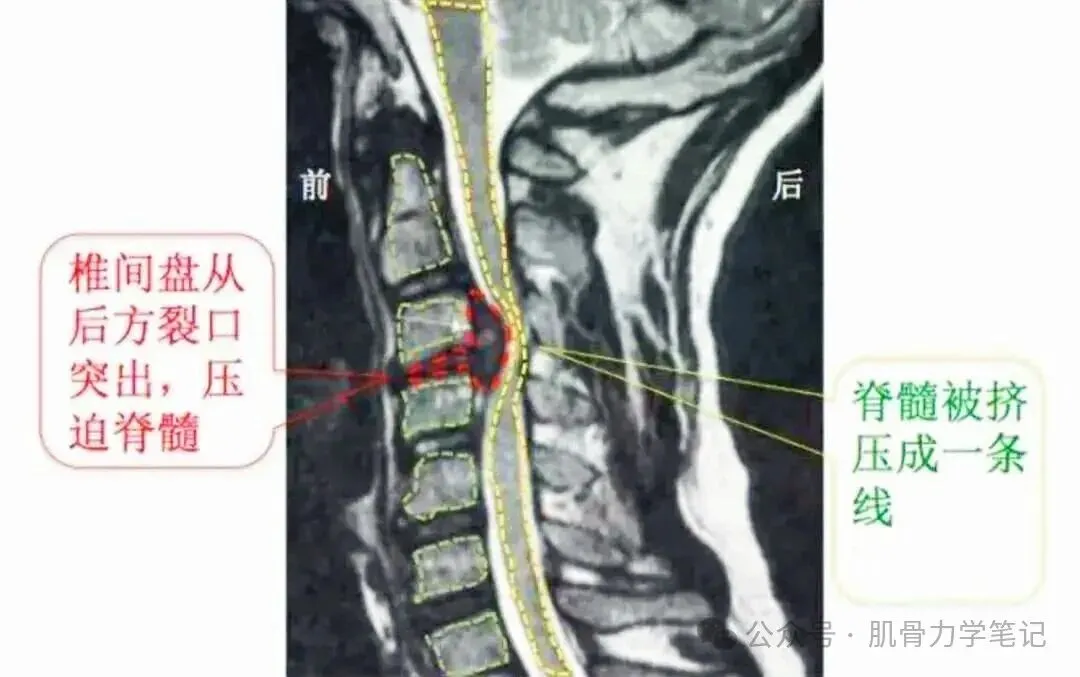

· CT/MRI:清晰显示椎间盘突出、神经根受压情况

· 脊髓型颈椎病